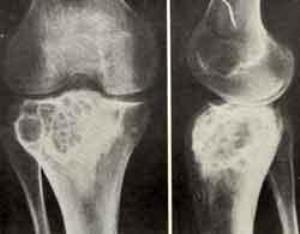

На рентгенографических снимках определяется локализованное просветление яйцеобразной либо круглой конфигурации, преимущественно на латеральной эпифизарной поверхности. В случае подхода к сухожильному слою происходит его полная деструкция. Опухолевый очаг с ровными, резкими границами. По периферии ободочек склератотического процесса. Корковый слой вздутый, иногда наблюдаются периостальные наслоения в метафизе. Иногда в очаге наблюдается разной интенсивности крапчатость, которая обусловлена известковым накоплением в хондробластомной массе.

При локализации между эпифизом и метафизом похоже на воспаление (абсцесс Броди). При смешении с гигантоклеточным новообразованием очаговая зона размещается в самой кости, полностью задействуя ее поперечник и способствуя вздутию и утончению коркового слоя по кругу кости. Хондромная форма характеризуется большими кальциевыми очагами, кистозная – большим количеством кист с отдельными внутренними полостями.

Первично малигнизированной и малигнизированной форме свойственны обширные фокусы разрушения, вплоть до коркового слоя.

Иногда ХБ по рентгенпроявлениям похожа на гигантоклеточную опухоль, хондросаркому либо остеогенную саркому, таким образом, с целью подтверждения постановки диагноза необходимо осуществление дополнительного обследования – биопсии через трепанацию либо радиационной индикации.